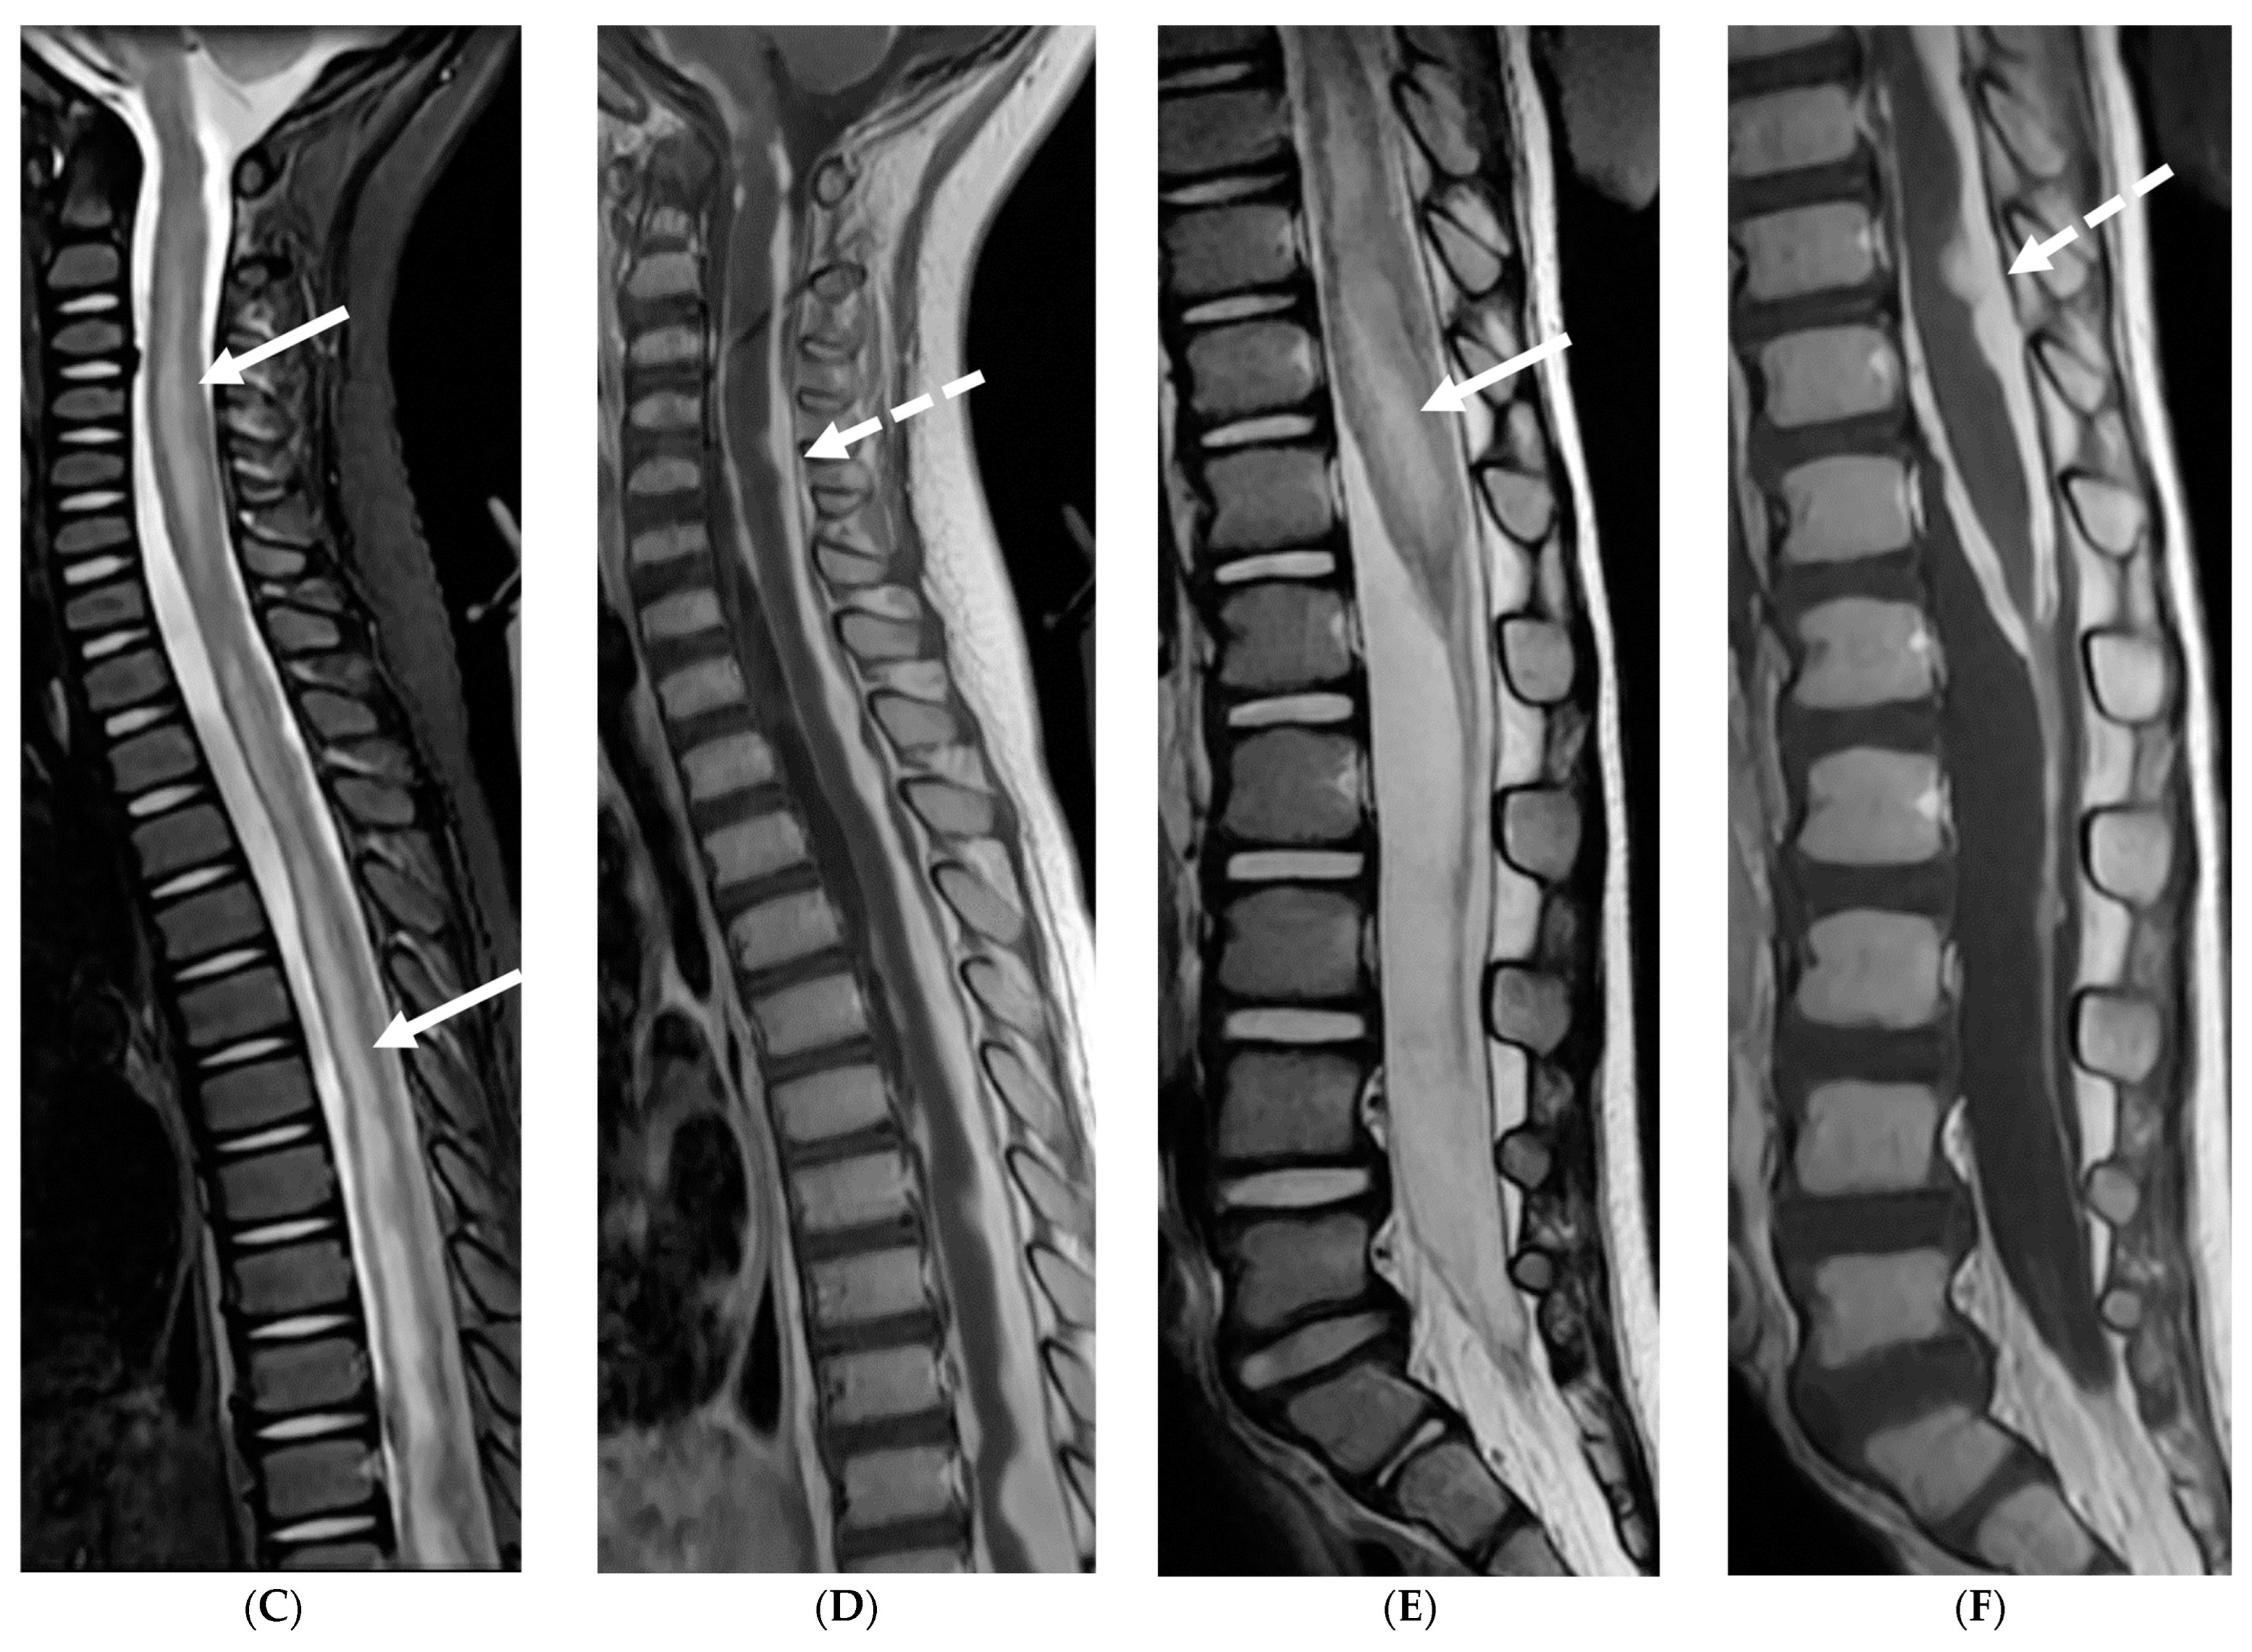

Common causes of leptomeningeal metastases from a pediatric intracranial primary tumor are medulloblastoma, embryonal tumor, ependymoma, germinoma, pineal tumor and atypical teratoid rhabdoid tumor. The primary theory suggests that tumor cells breach the pia mater and ependyma, gaining access to the cerebrospinal fluid (CSF). These cells then disseminate via the CSF, eventually settling along the spinal meninges [80]. The most common locations are thus, lower-thoracic and lumbar spine, located along the dorsal cord as CSF flow is from brain to the spine dorsally [81].

Currently, contrast-enhanced MRI and CSF cytology are the gold standards for detecting LM [82]. Key imaging findings include enhancing circumscribed nodule/s and/or irregular, thickened enhancement along the dorsal spine [81]. Pitfalls in detection of LM include vascular structures along the cord, seen as short segments of faint and thin enhancement. Veins are typically in midline, are tortuous and most prominently seen in high thoracic and conus medullaris regions (Figure 14). CSF flow artifacts can mimic LM on MRI, especially in the dorsal epidural space with a wide spinal canal. However, their epicenter in the subarachnoid space location can help distinguish them from true lesions [81,83]. MRI with 3D sequences offers superior sensitivity compared to CSF cytology, significantly reducing artifacts [80].

Figure 14.

Post contrast axial T1 (A) and sagittal T1 (B): 3-year-old girl presented with headache, vomiting for 2 weeks and new right sided weakness. Fourth ventricular mass (arrow) with leptomeningeal metastasis (curved arrows). Dural and leptomeningeal metastasis (dashed arrows). Pathology: Anaplastic Medulloblastoma. Axial T1 post contrast (C): 4-year-old girl with headache and vomiting for 2 weeks. There is a partially enhancing mass in the right anterior temporal lobe (arrow) with extensive basal and leptomeningeal metastasis (curved arrow). Pathology: Atypical Teratoid Rhabdoid tumor (ATRT). Axial T1 post contrast (D): 10-year-old boy with vomiting and headaches: There are synchronous tumors in the suprasellar (arrow) and pineal region with hydrocephalus. Subtle LME is seen in the superior vermis (curved arrows). Pathology: Germinoma.